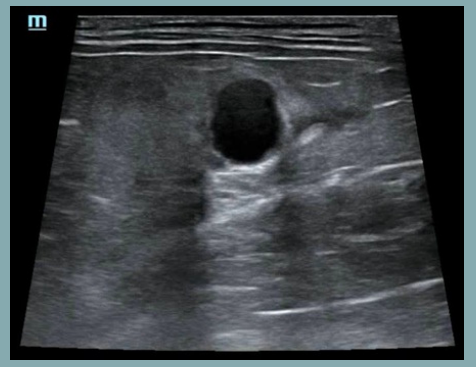

Artefactos: Refuerzo posterior

- Las ondas sonoras pasan a través de un tejido de baja densidad (fluido) y presentan una mayor intensidad respecto a otras ondas en el mismo plano de profundidad.

Artefactos: Sombra de borde

- Se forma en los bordes de estructuras curvas o redondeadas, como un quiste, un vaso sanguíneo o una lesión nodular.

- La imagen muestra una sombra longitudinal a cada lado del borde de la estructura redondeada, debido a la refracción de las ondas en el borde estructural.